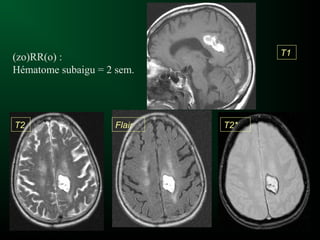

(zo)RR(o) :

Hématome subaigu = 2 sem.

T1

T2 Flair T2*

(zo)RR(o) : Hématome subaigu= 2 sem. T1 T2 Flair T2*